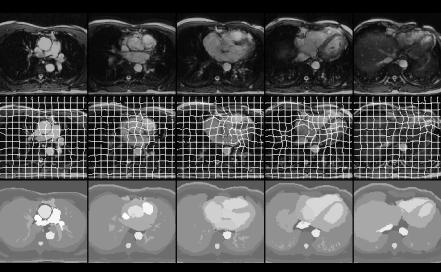

Another dynamic model representing 18 time instants of the cardiac cycle was constructed. The high quality full thorax 56 slice cine MR images with 18 time frames were acquired with an ECG-gated, gradient echo sequence, with steady-state free precession. The resolution was 256x256 with field of view 46x46cm. Due to the relatively small size of the test person the region from the neck to below the heart was imaged. The images were segmented with a two-stage procedure. At the first stage the first timeframe (T=1) of the slice set was segmented using the semiautomatic region growing based tools. At the second stage a method based on deformable models [5] utilizing the segmentation result of the first time instant was used to segment the rest 17 phases. Fig. 1 demonstrates a segmentation result for this set at time step (T=5). In 1a) the transformed model and the original MR set are shown using a chess-board visualization technique. If the match was not good, it would be seen as discontinuous edges in the picture. These discontinuities are hardly visible in the result. The transformation is visualized in Fig. 2 by an elastic grid superimposed on the data along with the segmentation result.

Figure1.  Model 2; segmentation at time step T=5 at five different levels of the image stack. a) The transformed model and the original MR volume are shown using a chess-board visualization, b) the transformation is visualized by an elastic grid superimposed on the data. c) the resulting segmentation.